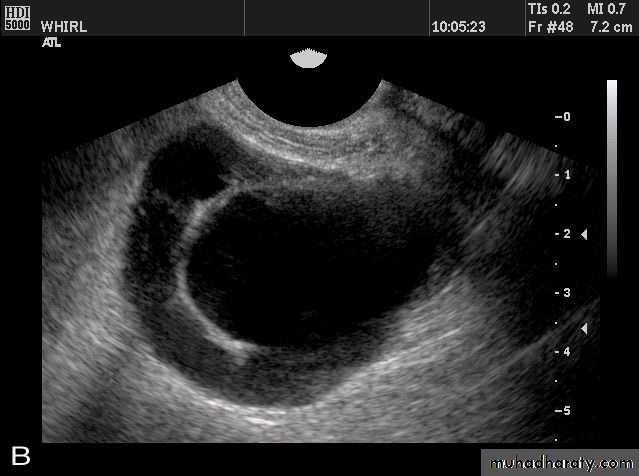

Ovarian hyperstimulation syndrome (OHSS):

This young adult female patient was examined to evaluate the uterus and ovaries. She was under treatment for infertility and was using gonadotropins. Ultrasound images of the ovaries show grossly enlarged ovaries with large cysts (measuring 2.6 to 3 cms.) in both ovaries. These ultrasound findings are diagnostic of OHSS or ovarian hyperstimulation syndrome.

• Ovarian hyperstimulation syndrome (OHSS):

The ultrasound image again show hyperstimulated ovaries. Both ovaries are grossly enlarged and cystic.

Transvaginal ultrasound images of ovarian hyperstimulation syndrome:This young adult female patient showed multiple large theca lutein cysts of both ovaries, arranged in spoke-wheel pattern (ultrasound images above) which were the result of use of gonadotropins in the management of infertility. The cysts vary in size from 2 to 4 cms. with the ovaries massively enlarged (each ovary measures up to 7 cms. in size). This can be classified as grade-2 hyperstimulation of the ovaries (ovarian diameter from 5 to 10 cms.). There is not evidence of ascites. The color Doppler image of the ovaries shows vessels passing along the margins of the cysts. One of the complications of such enlarged ovaries in OHSS is torsion and in certain cases rupture of the ovaries, both of which are medical emergencies. Ovarian hyperstimulation syndrome is known to occur more frequently in patients of pre-existing Polycystic ovaries (PCO).